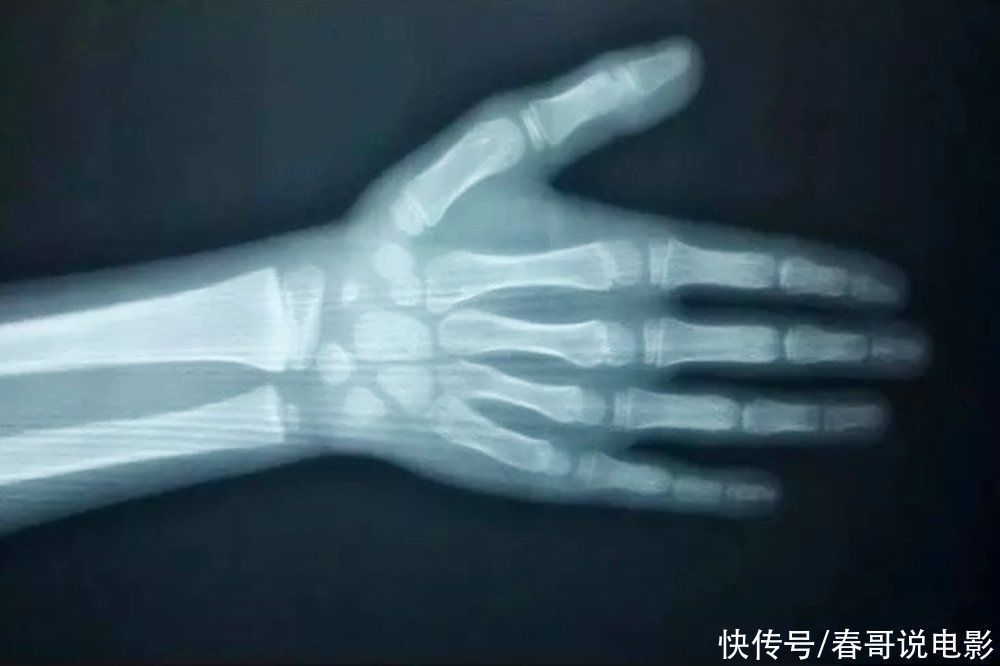

适当延长骨龄对于孩子的身高发育有什么意义?孩子身高能长到什么程度,往往取决于最后骨骼线的闭合时间。骨骼线闭合得早,自然身高不再生长,最后身高定型;而骨骼线闭合得晚,身高便仍然有增长的机会。

正常情况下,骨龄应该是和孩子的实际年龄相符合,但骨骼的发育也会受到饮食营养、睡眠、运动等多种因素的影响,因此骨龄更多时候会和实际年龄出现偏差,出现骨龄提前或者落后等情况。